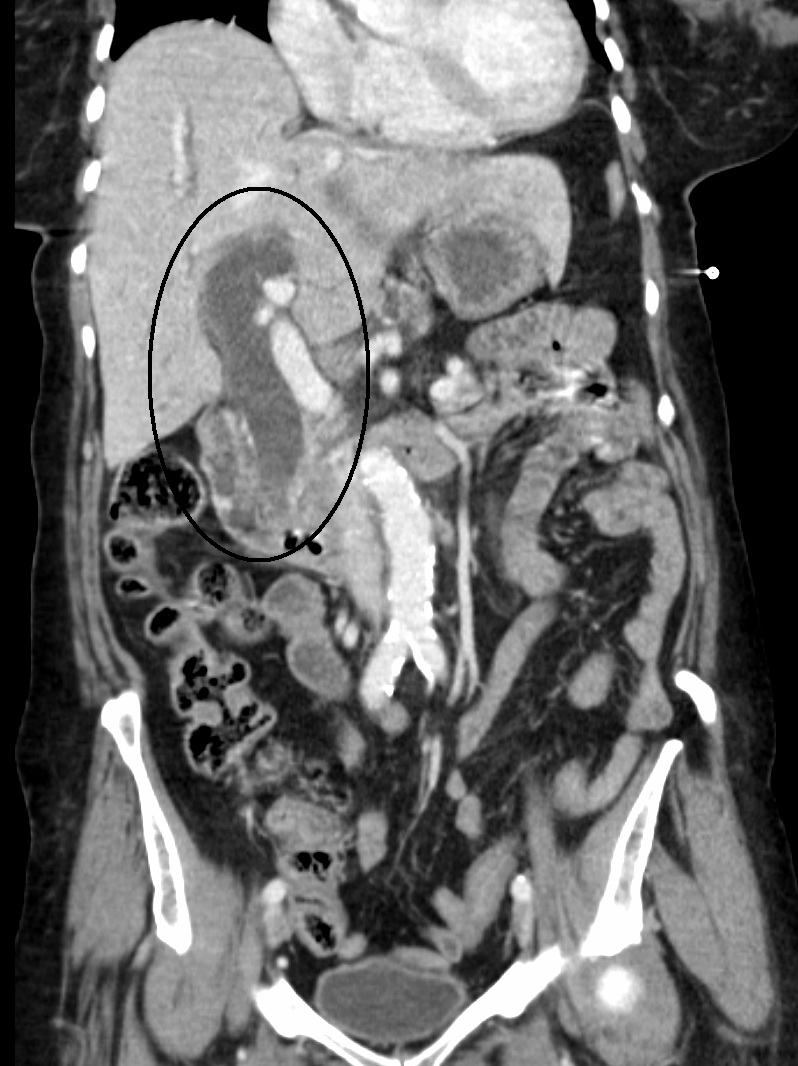

초음파, CT 스캔, HIDA 스캔과 같은 의료 영상 기법은 담관 폐쇄 여부를 확인하는 데 유용하다.[40]

초음파, CT 스캔, HIDA 스캔과 같은 의료 영상 기법은 담관 폐쇄를 감지하는 데 유용하다.[40]